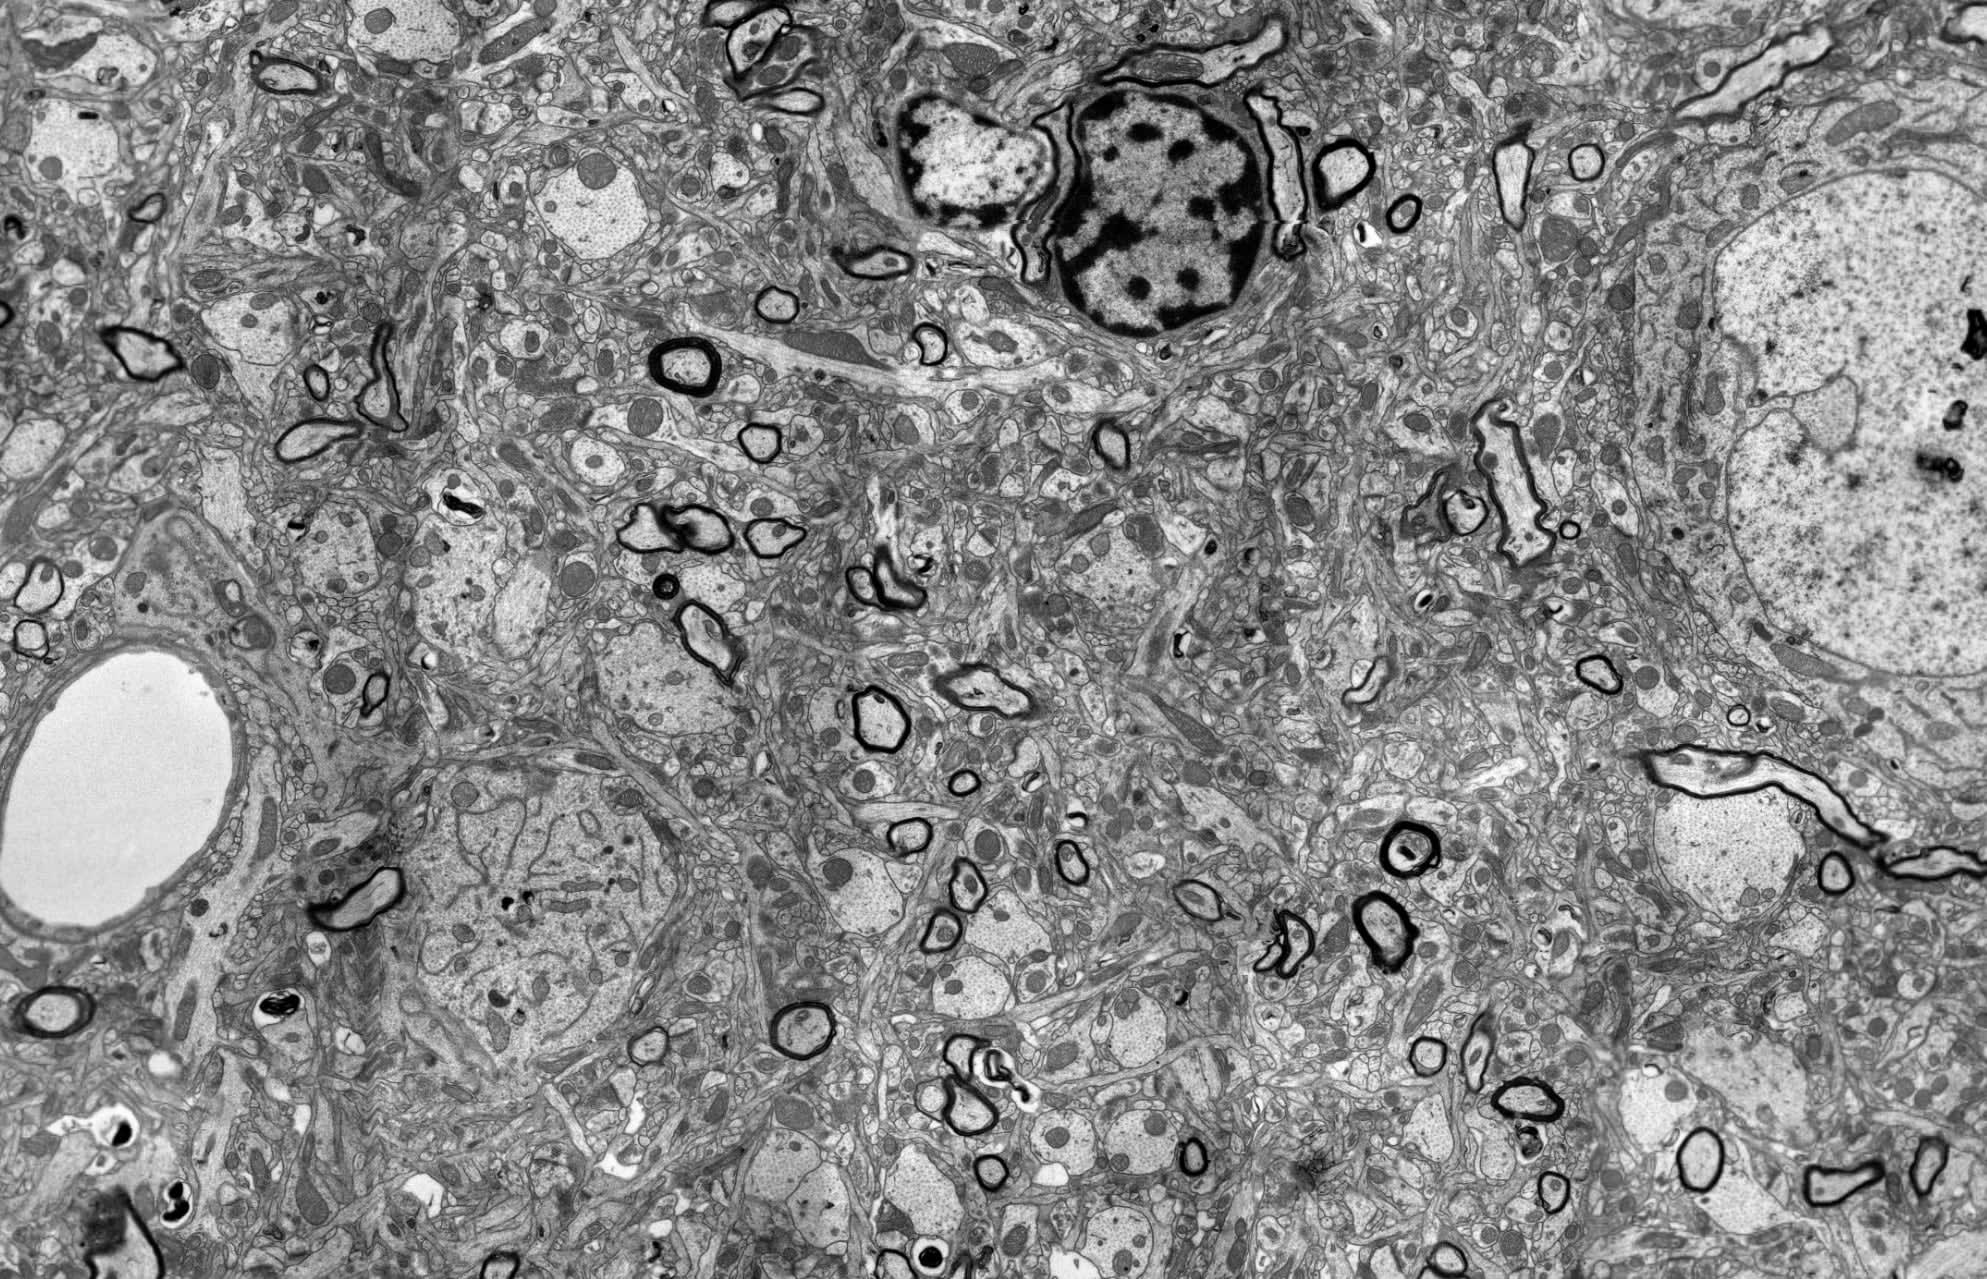

The images above are taken from the BPF’s Accreditation page. The left image is what “typical” brain tissue looks like—the kind that Ken and other neuroscientists are used to studying. The right image is a cryoprotected animal brain[1]. It looks more “swirly” because it’s been dehydrated by cryoprotectants. Ken started the Brain Preservation Prize, in part, to challenge the cryonics community to produce images more like the one on the left, so they could better evaluate whether their preservation techniques worked.

Of course, imaging a whole brain is well beyond our current capabilities. Ken compensated for this by analyzing many samples, randomly chosen from different regions of the brains. The BPF released all of the images and the original 3D data files, and they’re still available today. I’ve included the pig brains below – click through on the images to see youtube videos showing the 3D imaging in full. Each sample is from a brain that was preserved, vitrified, and rewarmed.

A 3D FIBSEM image of a pig brain preserved post-mortem. We were able to complete surgery in 4 minutes and 30 seconds, well within the critical twelve-minute window, and attained results that appear traceable. Additional results available as supplemental materials. Video linked below: